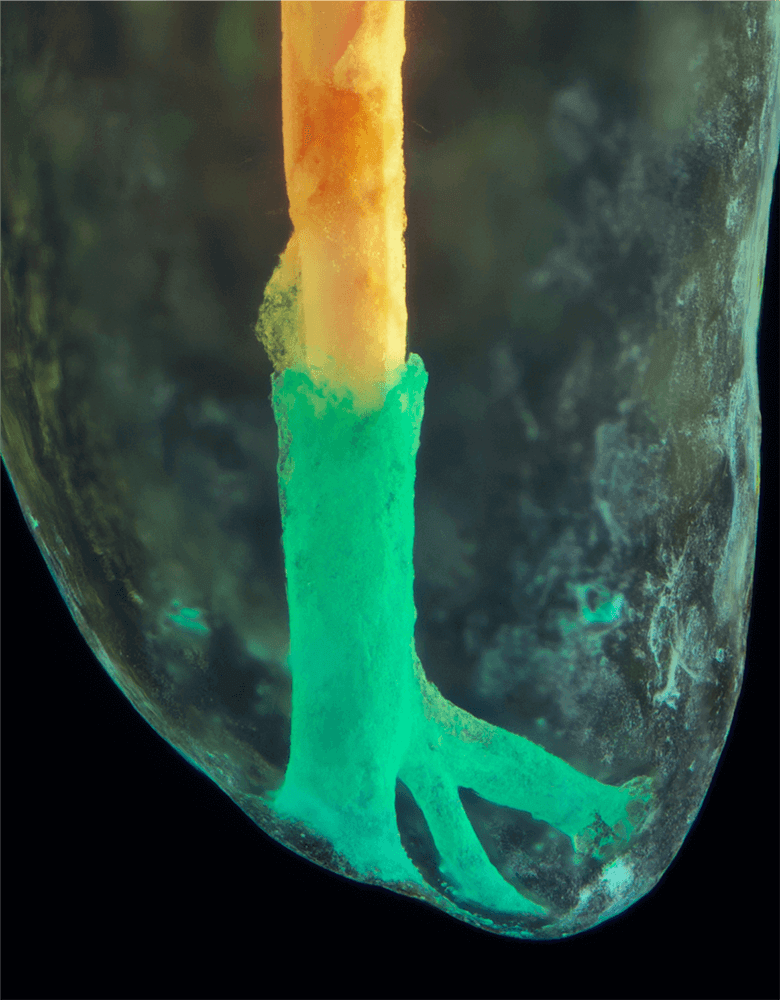

Transparente Zahnpräparate

Bilder transparenter Zahnpräparate

Das Verfahren, Zähne in durchsichtige Präparate zu überführen ist schon über 100 Jahre alt. Aber erst durch die Weiterentwicklung der alten Technik und die Kombination mit moderner Fotografie sowie der Entwicklung eines geeigneten Gefäßes zur Fotografie ist es meinem Vater Dr. Holm Reuver gelungen, einzigartige Bilder vom Inneren der Zähne aufzunehmen.

Die Bilder sind in verschiedenen Größen wählbar und auch als POPART-Variante erhältlich. Sie sind hervorragend geeignet für die Beratung von Patienten vor endodontischen Behandlungen, aber auch ein beliebter Eyecatcher im Wartezimmer. Außerdem haben die Bilder einen bedeutenden Stellenwert für die Erforschung der Pulpatopografie und für die Lehre im Bereich der Endodontie.

CLEARINGSERVICE bietet Ihnen die Möglichkeit, wurzelgefüllte Zähne mit der Technik des Transparentmachens untersuchen zu lassen. Das geht sehr einfach: Sie schicken uns den zu untersuchenden Zahn, dieser wird dann in ein transparentes Präparat überführt und mit hochwertiger Makrofotografie ausgewertet. Anschließend bekommen Sie die angefertigten Präparate zusammen mit der Fotodokumentation zugeschickt.